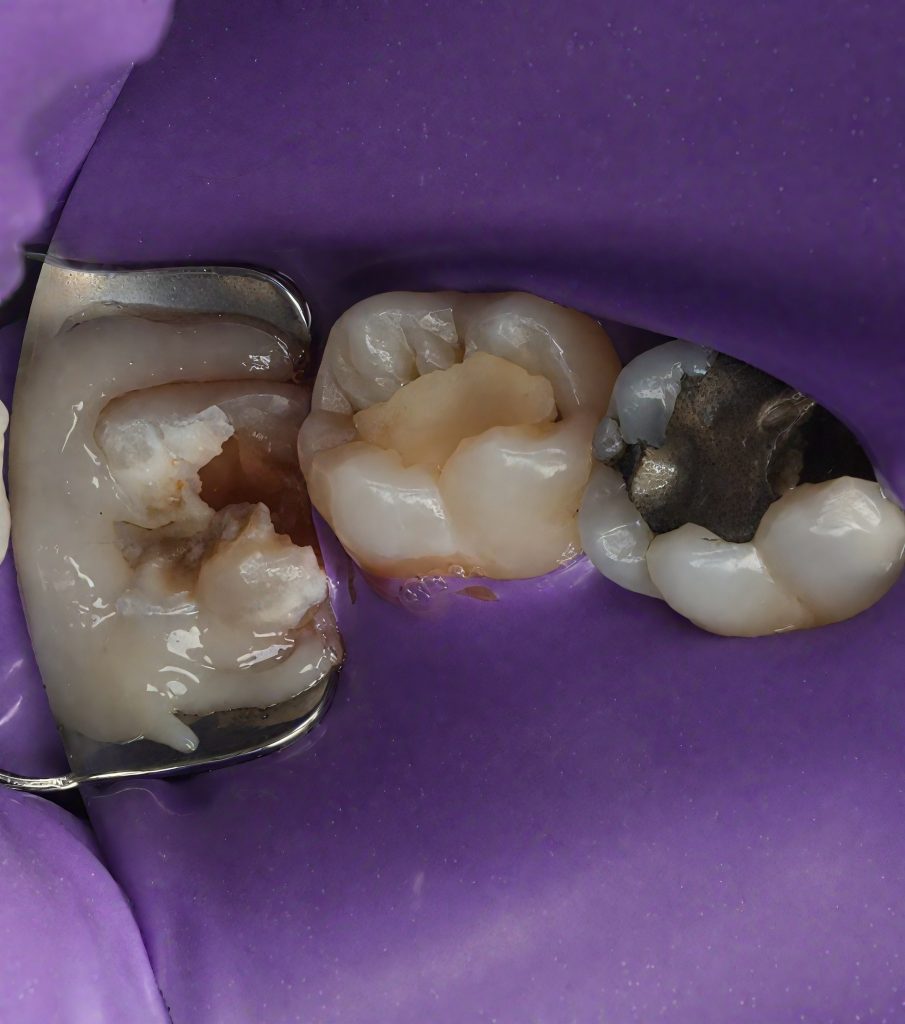

Due to limited access and infra-occlusion, rubber-dam isolation was achieved using a modified split-dam technique with floss ligatures and PTFE retraction (Fig 2). Microscope magnification allowed moisture control and precise visibility during adhesive procedures.

Caries excavation performed conservatively, preserving enamel ridges. Distal sub-gingival margin elevated using the Matrix-within-Matrix DME technique with a sectional matrix system and Teflon-assisted adaptation. This enabled proper contact form and a cleansable margin (Fig 3).

- Fig 2: Split-dam isolation under microscope.

- Fig 3: Deep marginal elevation with Matrix-within-Matrix technique.